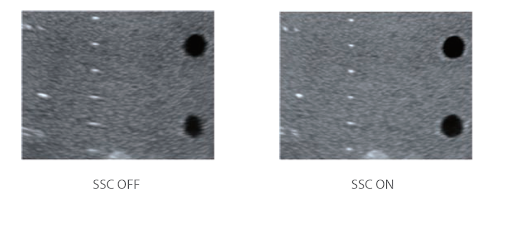

Компенсация скорости звука

С помощью ретроспективного анализа всех данных каналов, хранящихся в памяти, система может интеллектуально выбирать оптимальную скорость звука для повышения точности отображения каждого вида ткани, обеспечивая регулируемую тканеспецифическую оптимизацию.